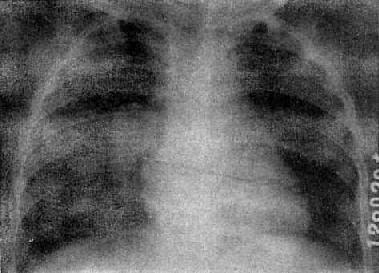

X线表现是病变多发生在两肺中、下野的内、中带。支气管及周围间质的炎变表现为肺纹理增多、增粗和模糊。小叶性渗出与实变则表现为沿肺纺理分布的斑片状模糊致密影,密度不均(图3-1-18)。密集的病变可融合成较大的片状。病变广泛可累及多个肺叶。小儿患者常见肺门影增大、模糊并常伴有局限性肺气肿。

图3-1-18 支气管肺炎

肺门影增大,肺纹理增强、模糊,中、下肺

野可见沿肺纹理分布的斑片状模糊致密影